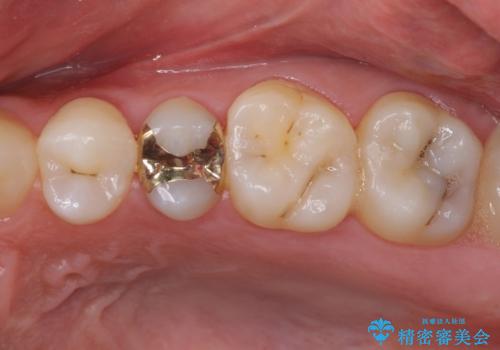

奥歯のクラウン周りが腫れる 精密治療による腫脹の改善